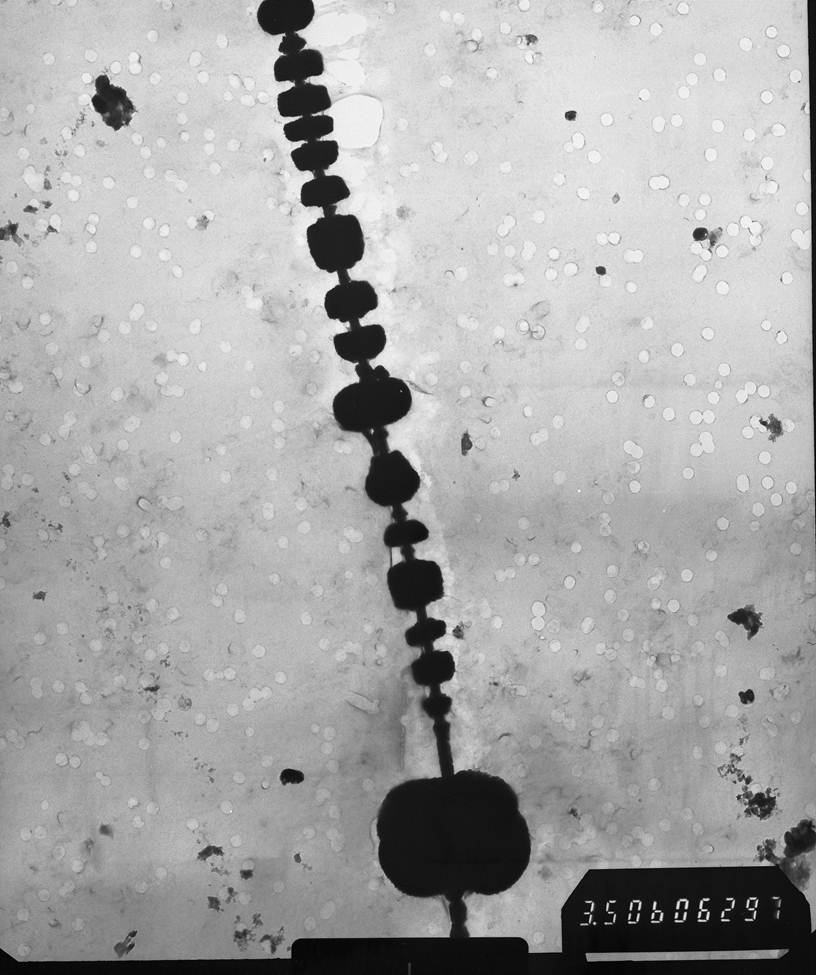

Ferruginous Body

Randy Nessler and Steve Landis